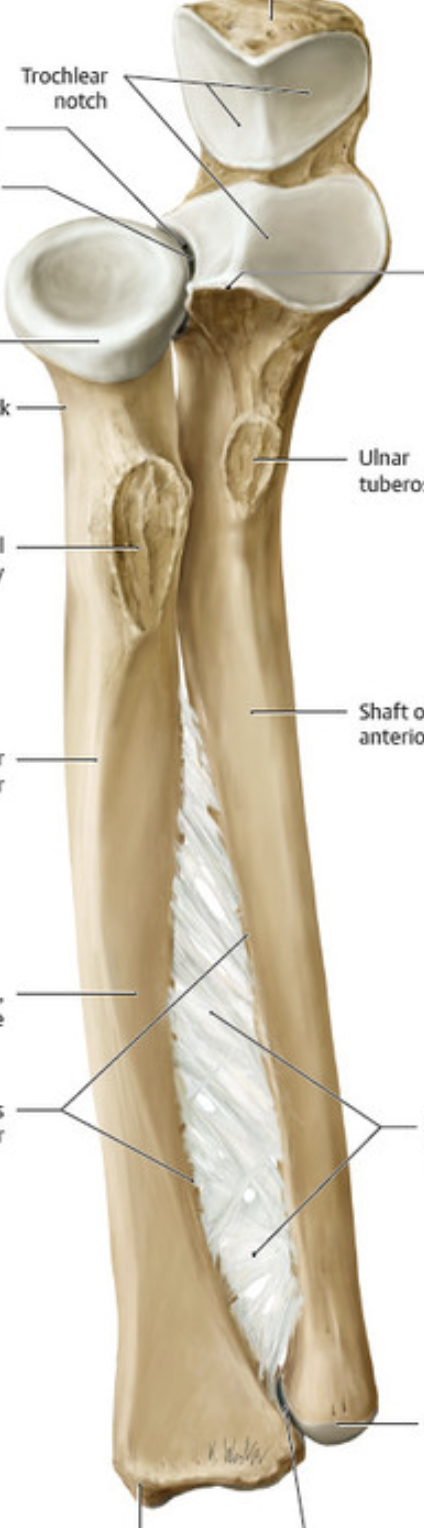

The head of the humerus articulates with the ___ at the ___ joint. The __ and ___ of the humerus articulate with the radius and ulna, respectively, at the elbow (cubital) joint.

The head of the humerus articulates with the scapula at the glenohumeral joint. The capitulum and trochlea of the humerus articulate with the radius and ulna, respectively, at the elbow (cubital) joint.